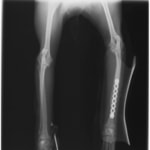

ペルシャ猫 11ヶ月齢 雄

他院にて左大腿骨遠位の成長板骨折(salter-harrisⅠ型)が認められており、治療相談を目的として来院。当院にて、キルシュナーワイヤーを用いたピンニングにより骨折部位の整復を行いました。術後の経過は良好で、現在も経過観察中です。

術後レントゲン

Arthrex社のターゲティングデバイスを用いてピンニングの位置を調整することで、確実な固定を行っています。当院ではこの手術器具以外にも、人の手術にも使用される様々な器具を導入し、手術精度を高め、また医療メーカーと新しい器具の開発、試作にも取り組んでおります。